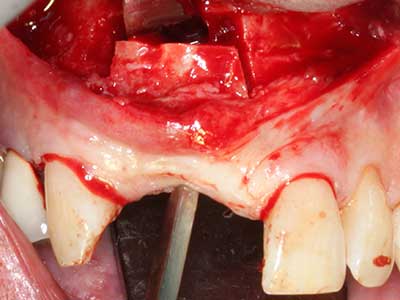

Piezosurgery has additional advantages when harvesting bone blocks. In addition to the high precision with osteotomy described above, the use of the thin saw tips specifically minimizes loss of material. Greater loss of material during harvesting can be expected with the thicker instrument tips, particularly when using Lindemann drills (Lakshmiganthan, Gokulanathan et al. 2012). The basal separation, which is necessary particularly for retromolar block transplants, is simplified by specially designed rectangular saws, with the result that piezosurgery is viewed as a precise, simple and safe procedure for harvesting retromolar bone blocks (Happe 2007) (Fig. 1-12).

Indication: Bone splitting

Bone tissue is not simply a mineral structure but also contains a substantial proportion of collagen fibres. This means it not only has good compressive strength but also a degree of flexibility, which can be taken advantage of when performing bone augmentations. In the classical expansion procedure using bone splitting, the atrophied alveolar ridge is split longitudinally and carefully expanded after reaching an adequate osteotomy depth (Fig. 13-16), ideally without substantial removal of the periosteum (Brugnami, Caiazzo et al. 2014, Stricker, Fleiner et al. 2014). Screw and plate systems with increasing expansion distance have proven effective in separating the two bone lamellae while remaining below the fracture threshold. In general, residual bone widths of at least 3–4 mm are required (Chiapasco, Zaniboni et al. 2006) to guarantee adequate flexibility and sufficient bone coverage of the future implants. If necessary, a vertical relief osteotomy on one or both sides can improve flexibility. A combination with additional augmentation techniques, particularly on the buccal side, has been described as an alternative to the classical technique.

The splitting procedure is particularly atraumatic and there is no significant loss of dimension when using piezosaws, and there are no significant differences between implants in split jaws and implants in an alveolar ridge without a bone deficit (Chiapasco, Zaniboni et al. 2006, Danza, Guidi et al. 2009). However, sufficient continuous irrigation is essential, particularly with locally restricted and deep splitting to prevent thermal stress in the apical osteotomy regions.